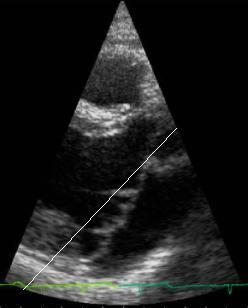

Here

is an animation clip of the acutal echocardiogram, showing

the prolapsing valve. The animation is paused at the prolapse

so that it can be clearly seen.

Click here for a larger, slow motion version The

image below captures the frame where the prolapse can most

clearly be seen. There is a line superimposed

over the approximate point where (according to the Cardiologists)

the valve should be stopping during a normal closure if

it

wasn't

prolapsing.

In other

words, the two leaflets shouldn't go to the right of the

line: